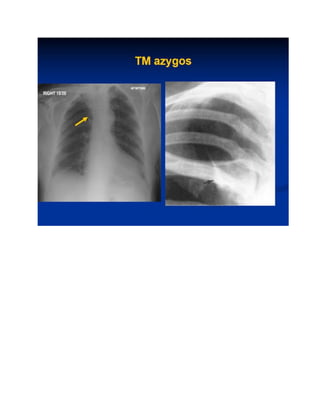

10 :TM Azygos

1: Khí quản 2:PQ gốc phải 3: PQ gốc trái 4: ĐMP trái 5:ĐMP thùy trên 6:ĐMP thùy dưới 7:PQ gốc trái 8: Cung ĐMC 9: Thân TM tay đầu 10 :TM Azygos